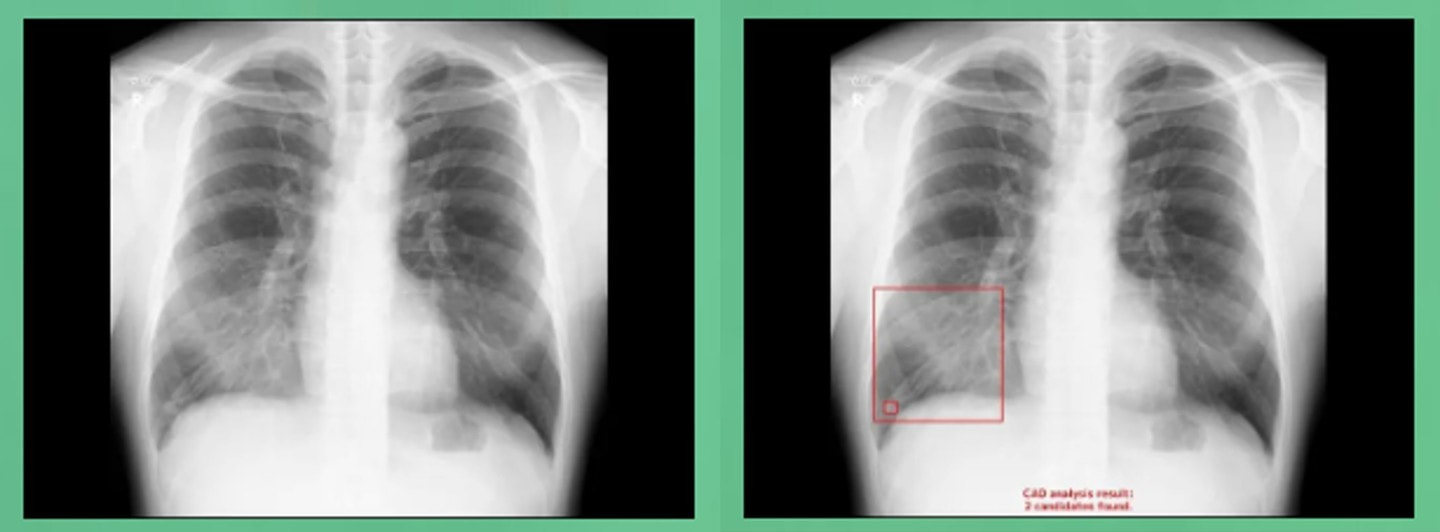

呼吸器 | 胸部X線 |

② 身体計測、血圧、採血、採尿、心電図、呼吸機能、聴力、腹部超音波、胃内視鏡、胸部レントゲン |